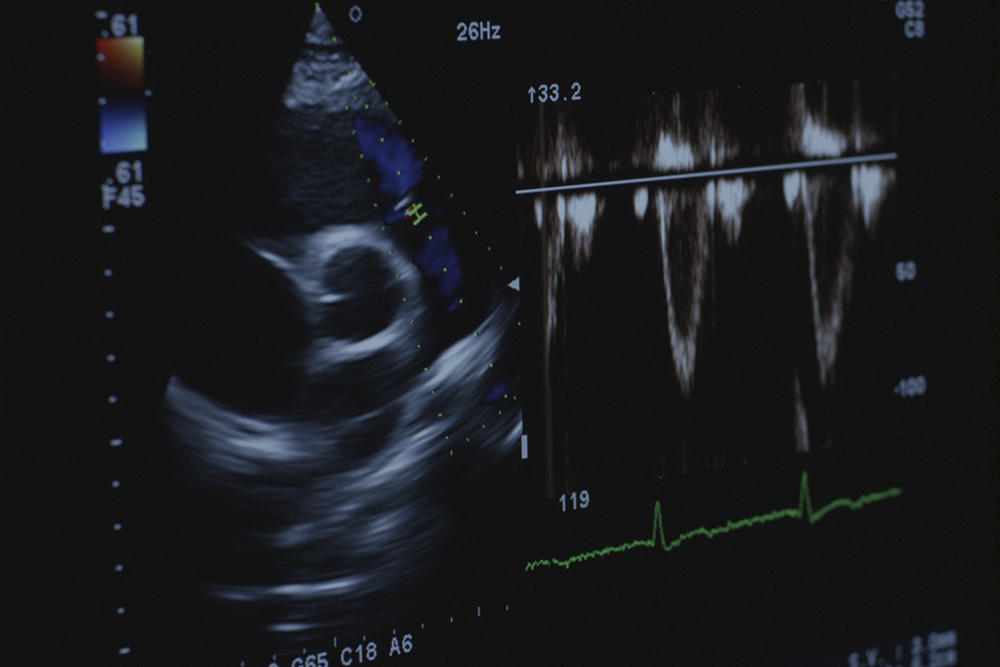

Los estudios del cuerpo realizados con ultrasonidos por personal experto y un equipamiento avanzado, permiten la producción de imágenes de calidad de cualquier parte del cuerpo humano. Un examen de ultrasonidos utiliza una instrumentación denominada transductores, los cuales introducen en los tejidos del cuerpo ondas de sonido de alta frecuencia que detectan los ecos producidos cuando estas saltan sus estructuras internas. Los diferentes tejidos del cuerpo reflejan los ecos de forma diferente y un software específico genera imágenes que se visualizan en el monitor y son analizadas por el radiólogo. Leer más...

4. Ecocardiograma Doppler color (diagnóstico cardiológico)